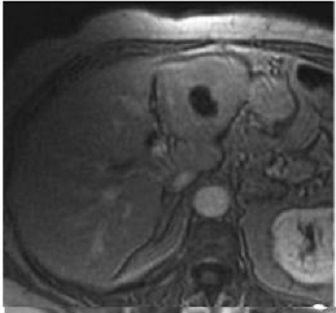

Image IRM de adenome du foie : Lesion est

hypersignal T1 et T2 par le caracteristique de la presence

de graisseux intracellulaire pres de 75% des cas .

Rehaussement important sur des zones non necrotique et non

hemorrhagique .

Áspect radiologique IRM

en T1 de adenome du foie droit : Image hypersignal

de multiple de adenome du foie gauche |

|

Même cas en T2 fat sat :

Image IRM T2 du foie en coupe axiale |